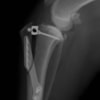

バーニーズマウンテンドック 4歳 避妊♀

突然の右後肢跛行を主訴に来院されました。整形外科学的検査において右膝に脛骨圧迫テストで陽性、前方引き出し徴候が認められました。神経学的検査において特に異常は認められませんでした。レントゲン検査において、関節液の貯留所見や脛骨の前方変位の所見が認められました。

関節鏡検査を実施いたしました。関節鏡検査では、重度の滑膜炎および前十字靭帯の完全断裂が認められました。半月板に損傷は認められませんでした。

断裂前十字靭帯の除去を行いました。その後 TTA(Tibial tuberosity advancement)を実施しました。

術後経過は良好で、後肢機能・筋肉量の改善目的で現在はリハビリテーションを行っています。